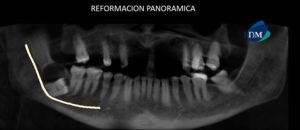

041 – Planificación y Tratamiento en Rehabilitación Oral con Prótesis sobre Implantes usando Análisis Cefalométrico

En los pacientes desdentados, que requieren una prótesis completa ya sea convencional o implanto soportada, los dientes artificiales se colocan en la prótesis completa por